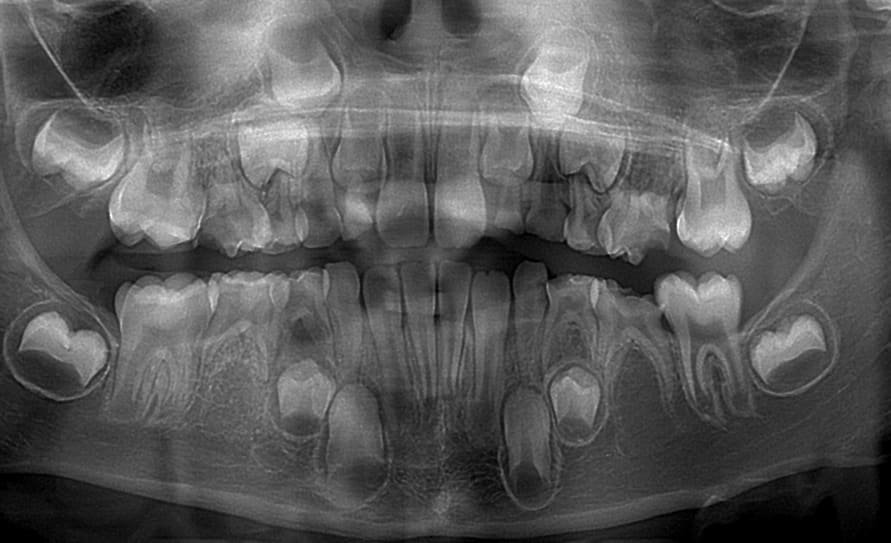

Gamin de huit ans.

A vu un confrère il y a deux ans pour les caries sur dents de devant.

Pas eu de soins ("les dents vont tomber")

La maman reprend un rdv "parce que plein de caries sont apparues d'un coup au fond"

La soeur ainé a eu beaucoup de soins lourds (extractions multiples de dents de lait).

"Les bonbons les bonbons les bonbons"

Alors là je suis bien emmerdé: 55 65 sont foutues (effondrement complet moitié distale de la dent avec gencive dans la cavité, douleurs à la percussion)

75 est quasiment à raz la gencive mais test au froid normal.

Les 46, 26, 16 ne sont toujours pas sorties.

Les orthos, je vais gérer comment les agénésies des 5 ? Je dégage les quatre 5 de lait au plus vite en priant pour que les 6 viennent boucher l'espace ?